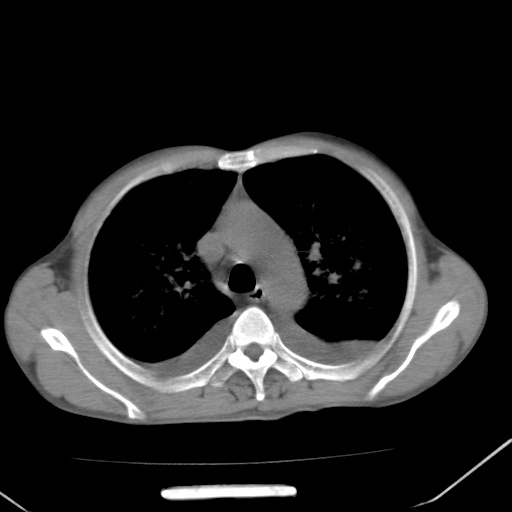

男、42岁、咯血3天。既往有甲亢、贫血、血尿蛋白尿史多年。血象:wbc:6.   中性粒:70.6%。

双肺野对称性磨玻璃影,分布于内中带,双侧胸水,患者有咯血。

双肺野广泛对称性磨玻璃影、实变影,以肺门为中心,主要分布于内中带,符合典型肺泡性肺水肿;伴双侧胸腔少量游离积液。结合患者既往病史且咯血就诊,支持多因素(尿毒症等)所致之肺水肿、肺出血、胸水;影像表现暂不考虑心源性水肿,且症状也不太符。需密切随诊结合临床治疗等进一步明确。

心影增大密度略低,双肺磨玻璃样高密度影及双侧胸腔积液,考虑心功能不全继发双肺肺水肿及双侧胸腔积液。心影密度略低,考虑贫血所致。